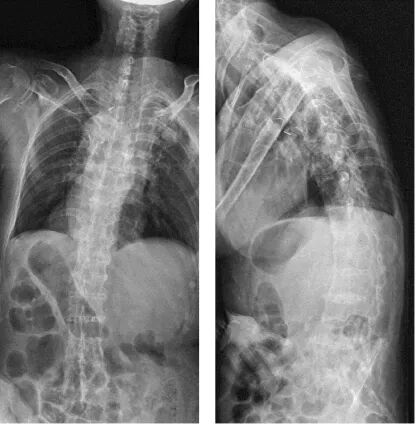

图3. CT检查结果

图3. PET-CT检查结果

2021.07.15 CT:手术部位成骨性改变,无明显肿瘤复发。

本例患者为肺癌术后伴全身多发骨转移,入院时胸背部疼痛,双下肢感觉运动障碍,无法行走。对患者给予一次地舒单抗,行手术治疗,患者自觉疼痛缓解,双下肢感觉运动明显恢复,手术后行地舒单抗治疗,并联合局部放疗、靶向治疗,复查影像学检查提示手术部位成骨性改变,无明显肿瘤复发,碱性磷酸酶显著降低。